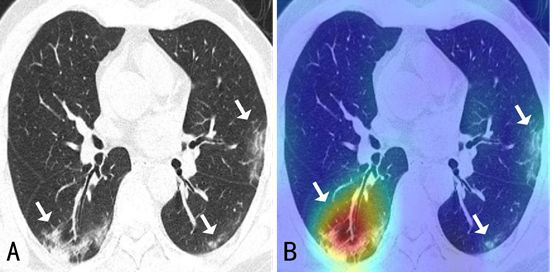

A: CT chest scan; B: Visual feedback from the AI system

The advantage of AI over the human eye, of course, lies in its efficiency. With Fudan’s AI system, lesions can be located within seconds while it takes a human radiologist 5-10 minutes.

Currently, a major problem with COVID-19 diagnosis is accuracy, as other types of pneumonia may lead to similar visuals, such as ground-glass opacities. However, Xue said, the location of lesions in the lung has been confirmed as a vital indicator to differentiate COVID-19 from other types of pneumonia.